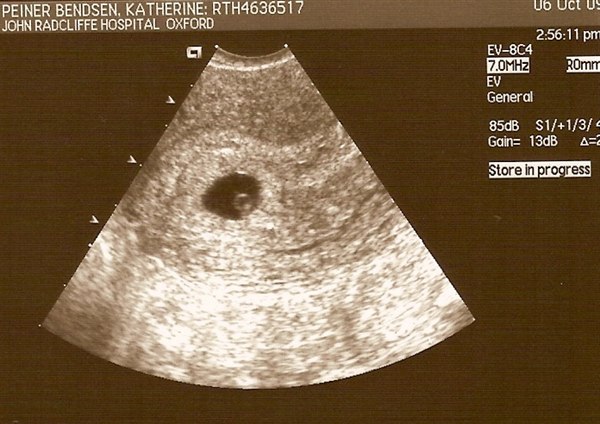

Jeg skulle til undersøgelses-scanning på sygehuset for at blive undersøgt for PCO. Da jeg var til scanning, var jeg gået 6 uger over tid og tænkte, at min menstruation blot var forsinket igen, som den altid var og havde været det igennem det sidste 1 1/2 år.

Sygeplejersken begyndte scanningen af min livmoder og æggestokke. Efter et par minutter vendte hun skærmen mod mig. På skærmen sås en lille rund cirkel, som lå i min livmoder. ”Sådan en ses normalt kun i forbindelse med graviditet”, sagde hun. Spørg lige om jeg blev overrasket. Herefter foretog hun en indvendig scanning, som bekræftede, at jeg var gravid i ca. 6. uge. Det var helt tydeligt at der var liv i min mave. Et lille hjerte, som bankede med al hast, kunne tydeligt ses.

Efter scanningen skulle jeg hente min kæreste, som havde fået fri fra arbejde. Han havde helt glemt, at jeg skulle på hospitalet, men kom i tanke om det, som han satte sig ind i bilen. Han blev ret så mundlam, da jeg under køreturen hjem viste ham scannings billedet af vores kommende barn. Jeg selv var ved at køre af vejen, da jeg forsøgte at forklare hvad som var hvad på billedet.